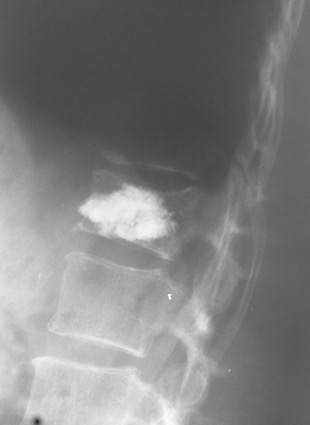

Пример компрессионного перелома тела второго поясничного позвонка у пожилой пациентки с остеопорозом после низкоэнергетической травмы (поскользнулась и упала на улице)

РЕЗУЛЬТАТ ОПЕРАТИВНОГО ЛЕЧЕНИЯ. ПОВРЕЖДЕННЫЙ ПОЗВОНОК ЗАПОЛНЕН КОСТНЫМ ЦЕМЕНТОМ. МЕТОДИКА ПОЗВОЛЯЕТ БЫСТРО КУПИРОВАТЬ БОЛЕВОЙ СИНДРОМ, НАЧАТЬ РАННЮЮ АКТИВИЗАЦИЮ ПАЦИЕНТА, ИСКЛЮЧИТЬ ПРОГРЕССИРОВАНИЕ ДЕФОРМАЦИИ